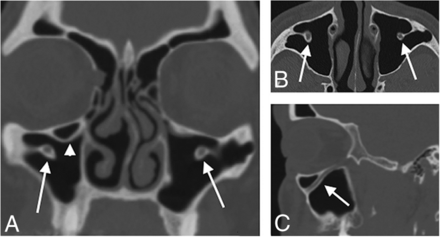

Axial (A), right parasagittal (B), and left parasagittal (C) sinus CT images in a 55-year-old woman show unilateral right-sided protrusion of the ION into the maxillary sinus (arrowhead in A and B). While part of the wall of the left IOC protrudes into the sinus, the entire circumference of the IOC is not distinct from the anterior maxillary sinus wall; this feature is confirmed on the sagittal image through the left maxillary sinus (arrows in A and C). Additionally, no measurable bony septum connects the IOC to the wall of the maxillary sinus. This distinction was chosen to define protrusion of the ION into the maxillary sinus.